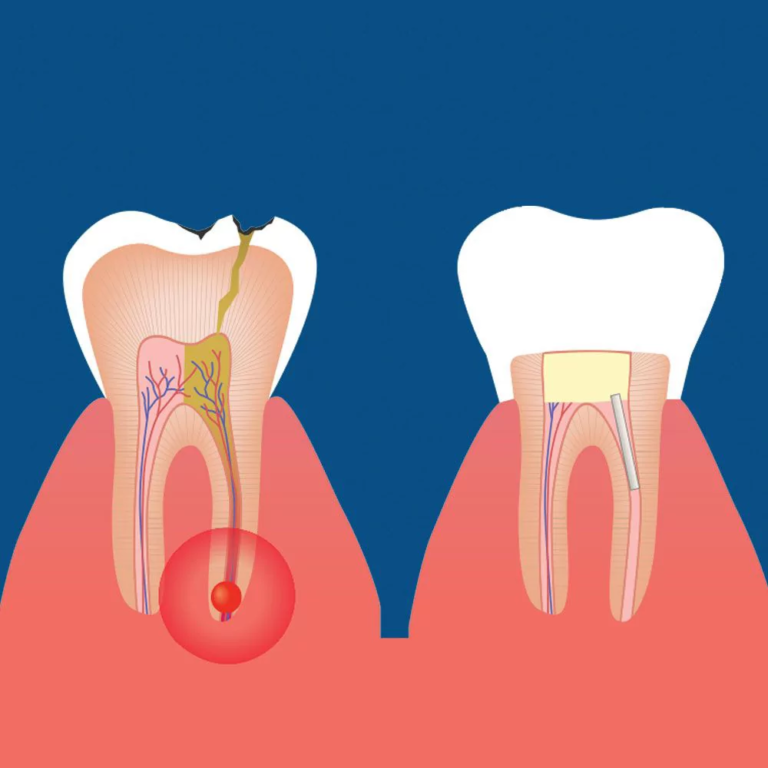

Root canal therapy—also known as endodontic treatment—is a procedure used to treat infection or inflammation of the tooth’s pulp, the soft tissue at the center that contains nerves and blood vessels. Infections can result from deep decay, trauma, cracks, or repeated dental procedures. If left untreated, they can lead to severe pain, swelling, abscesses, and tooth loss.

Following the removal of the infected pulp, the canal is meticulously shaped, disinfected, and sealed with a biocompatible material to prevent future reinfection.

- Tooth Restoration & Crown Placement

Once the root canal therapy is completed, the tooth is strengthened with a tooth-colored filling material. In most cases, a custom crown is recommended to protect the treated tooth from potential fractures. Your crown will be expertly color-matched and crafted to ensure long-lasting functionality and a natural appearance.